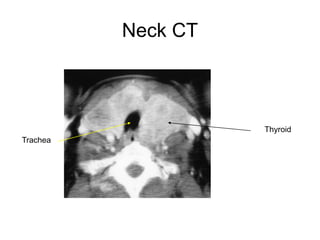

Neck CT

Thyroid

Trachea